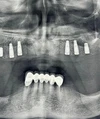

علاج الزرعات السنية